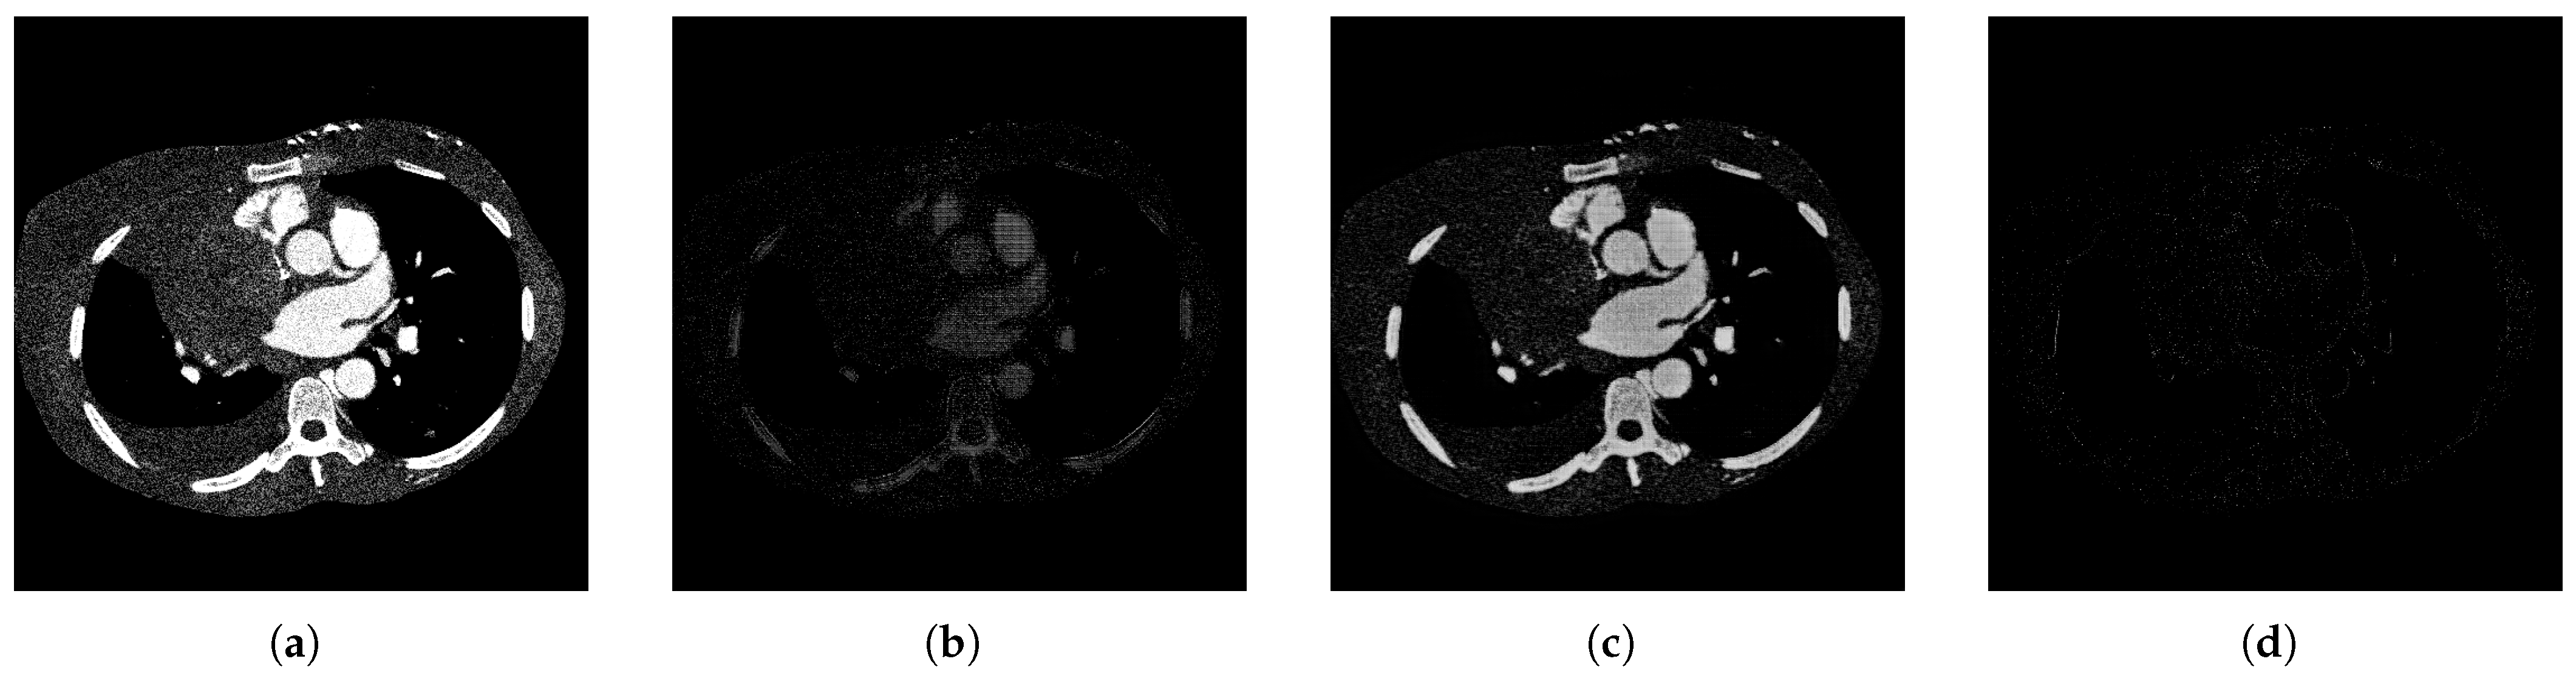

The qualitative performance of the proposed decomposition process is illustrated in Figure 6, which shows how the original image is separated into three semantically meaningful layers: a smooth layer capturing coarse structural information, a detail layer emphasizing fine textures and edges, and a residual layer isolating noise and unstructured content. As expected, the residual layer appears mostly sparse, confirming that most relevant information is effectively captured by the first two layers.

Figure 6. Visual representation of the image decomposition process using the proposed method: (a) Original input image, (b) smooth layer output, (c) detail layer output, (d) residual layer output.